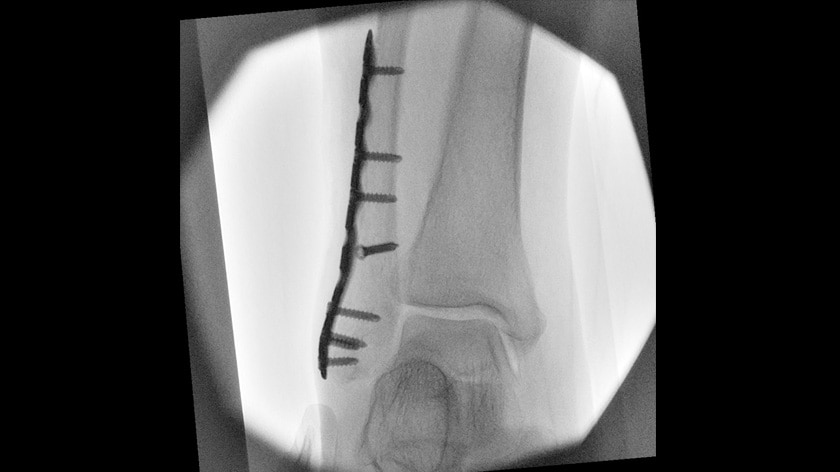

OPESCOPE ACTENO FD type, the mobile C-arm imaging system, provides free and easy positioning that achieves performance to meet the demands of the operation room and emergency room. The high-resolution FPD takes Surgical Imaging to new levels.

- Emergency/Trauma

- Surgery/ICU